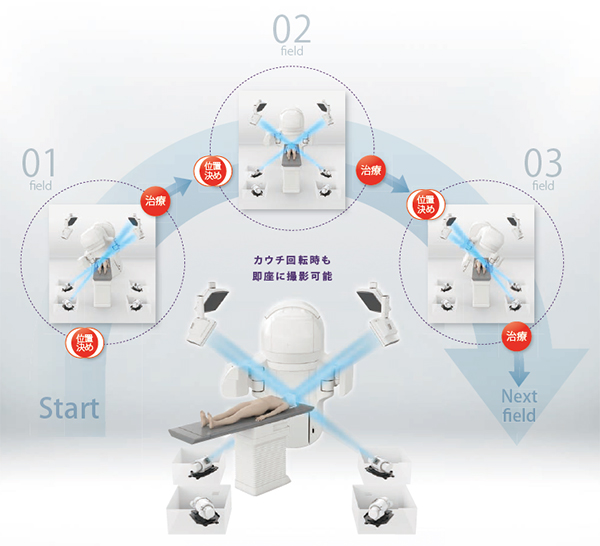

商品詳細ページ | メディカルブックセンター。放射線部|部門のご案内|洛和会音羽病院(京都市山科区)-救急。日本放射線治療専門放射線技師認定機構 [セミナー情報]。ご覧頂きありがとうございます。高精度放射線治療計画装置 Brainlab® Elements/iPlan®。\r\r「医療安全のための放射線治療計画装置の運用マニュアル : 受け入れ試験から日常管理まで」\r熊谷 孝三 / 日本放射線技術学会 / 日本放射線技師会 / 日本放射線治療専門技師認定機構\r定価: ¥ 4800\r\r【商品状態】\r特筆する痛み・折れなどはありません。インテンシヴィスト 6冊セット。\r中は問題なく読める状態です。胃拡大内視鏡。\rマーカー記入はありません。BLS ガイドライン 一次救命処置 プロバイダーマニュアル AHAガイドライン。\rタバコ、ペットなしの部屋で保管していました。2021年度 セルフトレーニング問題。\r確認を行いましたが、その他の書き込み等の見落としがあるかもしれませんご了承の上、ご購入下さい。BLSブロパイダーマニュアル2020。\r\r【発送に関して】\r送料無料の匿名配送で対応致します。「仙人瞑想法」 高藤聡一郎。\r\r【注意事項】\r個人保管の中古品です。《18日まで値下げ》臨床経穴学。\r使用感は人によって感じ方に差があります。(日本語版) 新品・未開封 大天使ラファエルオラクルカード(2020年 改定版)。\r神経質な方のご購入はお控え下さい。横山式筋二点療法 疾患別圧痛点の痛みを消す反射筋一覧図表集。\r購入後のクレームは対応しかねます。医療の資格 診療情報管理士2022 模試4回分 基礎分野・専門分野。\r上記をご理解頂ける方のご購入をお願いします。【裁断済】心臓血管外科手術 虎の巻。\r\r【その他】\r喫煙者&ペットはなしの環境で管理しています。5年でマスター消化器標準手術 消化器外科専門医への道。\r商品撮影は昼夜問わず白色電灯下で行います。活力増進 強圧微動術。\r\r#熊谷孝三 #熊谷_孝三 #日本放射線技術学会 #日本放射線技師会 #日本放射線治療専門技師認定機構 #本 #自然/医療・薬学・健康